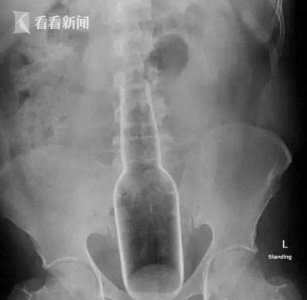

- 他们往下面塞的这些东西,竟藏着成年人“羞于启齿”的秘密...